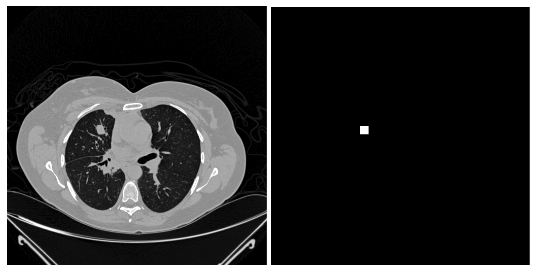

Refer to caption

Figure 1: a) Original CT image, b) generated ground truth mask.

We used the existing LUNA data set to train the model for lung nodule segmentation  [17]. The data set included 888 CT images. The LIDC/IDRI database also contains annotations which were collected during a two-phase annotation process using four experienced radiologists. Each radiologist marked lesions as they identified as non-nodule, nodule <3 mm, and nodules \geq 3 mm. The reference standard of our challenge consists of all nodules \geq 3 mm accepted by at least 3 out of 4 radiologists. Annotations that are not included in the reference standard (non-nodules, nodules <3 mm, and nodules annotated by only 1 or 2 radiologists) are referred as irrelevant findings. The ground truth mask for each of the cancerous nodules was generated by using the nodule centre and the diameter value of the image pixels indicated in the annotation file. The annotation file is stored as a csv file that contains one finding per line. Each line holds the SeriesInstanceUID of the scan, the world coordinate pixels x, y and z position of each finding and the corresponding diameter in mm. The annotation file contains 1186 nodules. The corresponding nodule centre and diameter value for the image pixels were turned into white and the remaining pixels were turned into black as shown in Fig 1.